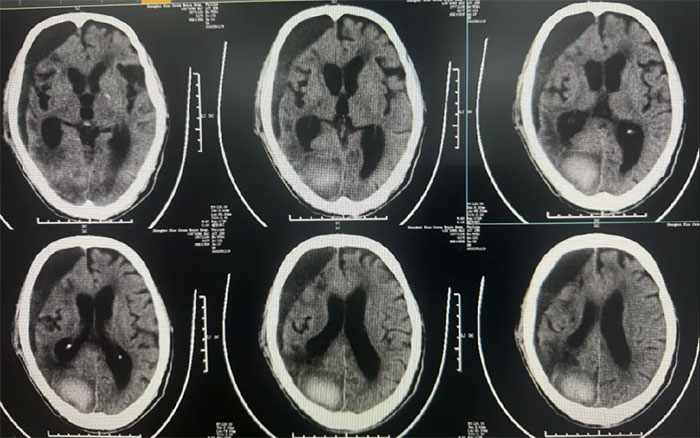

術后中線偏移明顯改善,顱內(nèi)壓降低,停用脫水藥物;

● 硬膜下血腫引流15天后拔管,中線基本復位,硬膜下血腫較前明顯減少;

● 患者神志昏迷,自動睜眼,無發(fā)聲,肢體刺痛躲避。GCS評分:9分;

● 無明顯顱內(nèi)感染,生命體征平穩(wěn)。